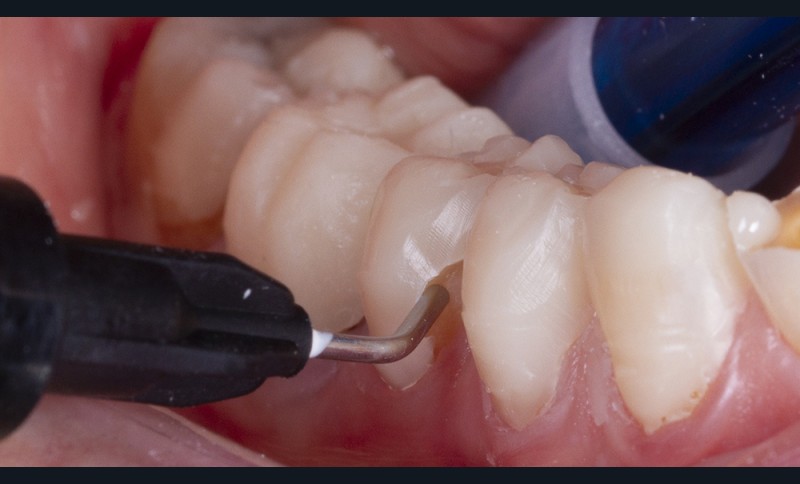

Un polissage des surfaces résineuses est nécessaire pour finaliser la temporisation (fig. 7).

Le calage postérieur obtenu assure l’augmentation de la DVO et entraîne très souvent une béance antérieure avec une perte du guidage antérieur (fig. 8). Le traitement du groupe incisivo-canin est alors nécessaire.